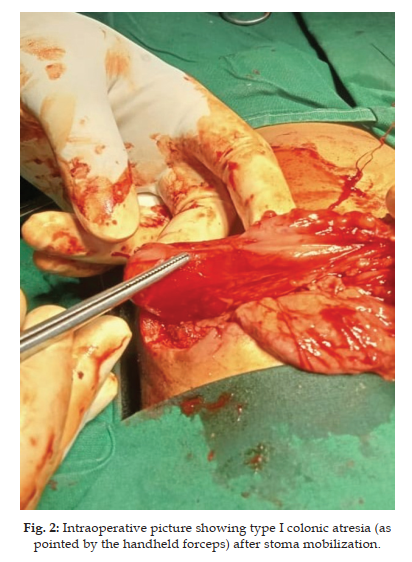

Obstructions in the lower intestinal tract, specifically colonic and rectal atresias, are distinct conditions that share similarities but necessitate different surgical interventions. Most of our understanding regarding these malformations is derived from isolated Case Report and a limited number of comprehensive investigations. Rectal atresia is a rare congenital anomaly characterized by a normal anus but an obstructed rectum. Its cooccurrence with other digestive system abnormalities, particularly colonic atresia, is even less frequent. We present an unusual case in which rectal atresia is observed in conjunction with colonic atresia, which was not detected during the initial surgical procedure. Contrast enema revealed only 2 cm of the anal canal from the distal end. The infant underwent surgical intervention for rectal atresia via the posterior sagittal approach. An end-to-end anastomosis was performed following resection of the atretic segment. Postoperatively, the patient was maintained on a regimen of regular Hegar's dilatation. Rectal atresia with colonic atresia is an exceedingly rare anomaly with very few cases reported in the literature. Awareness of such coexistence may minimize further complications